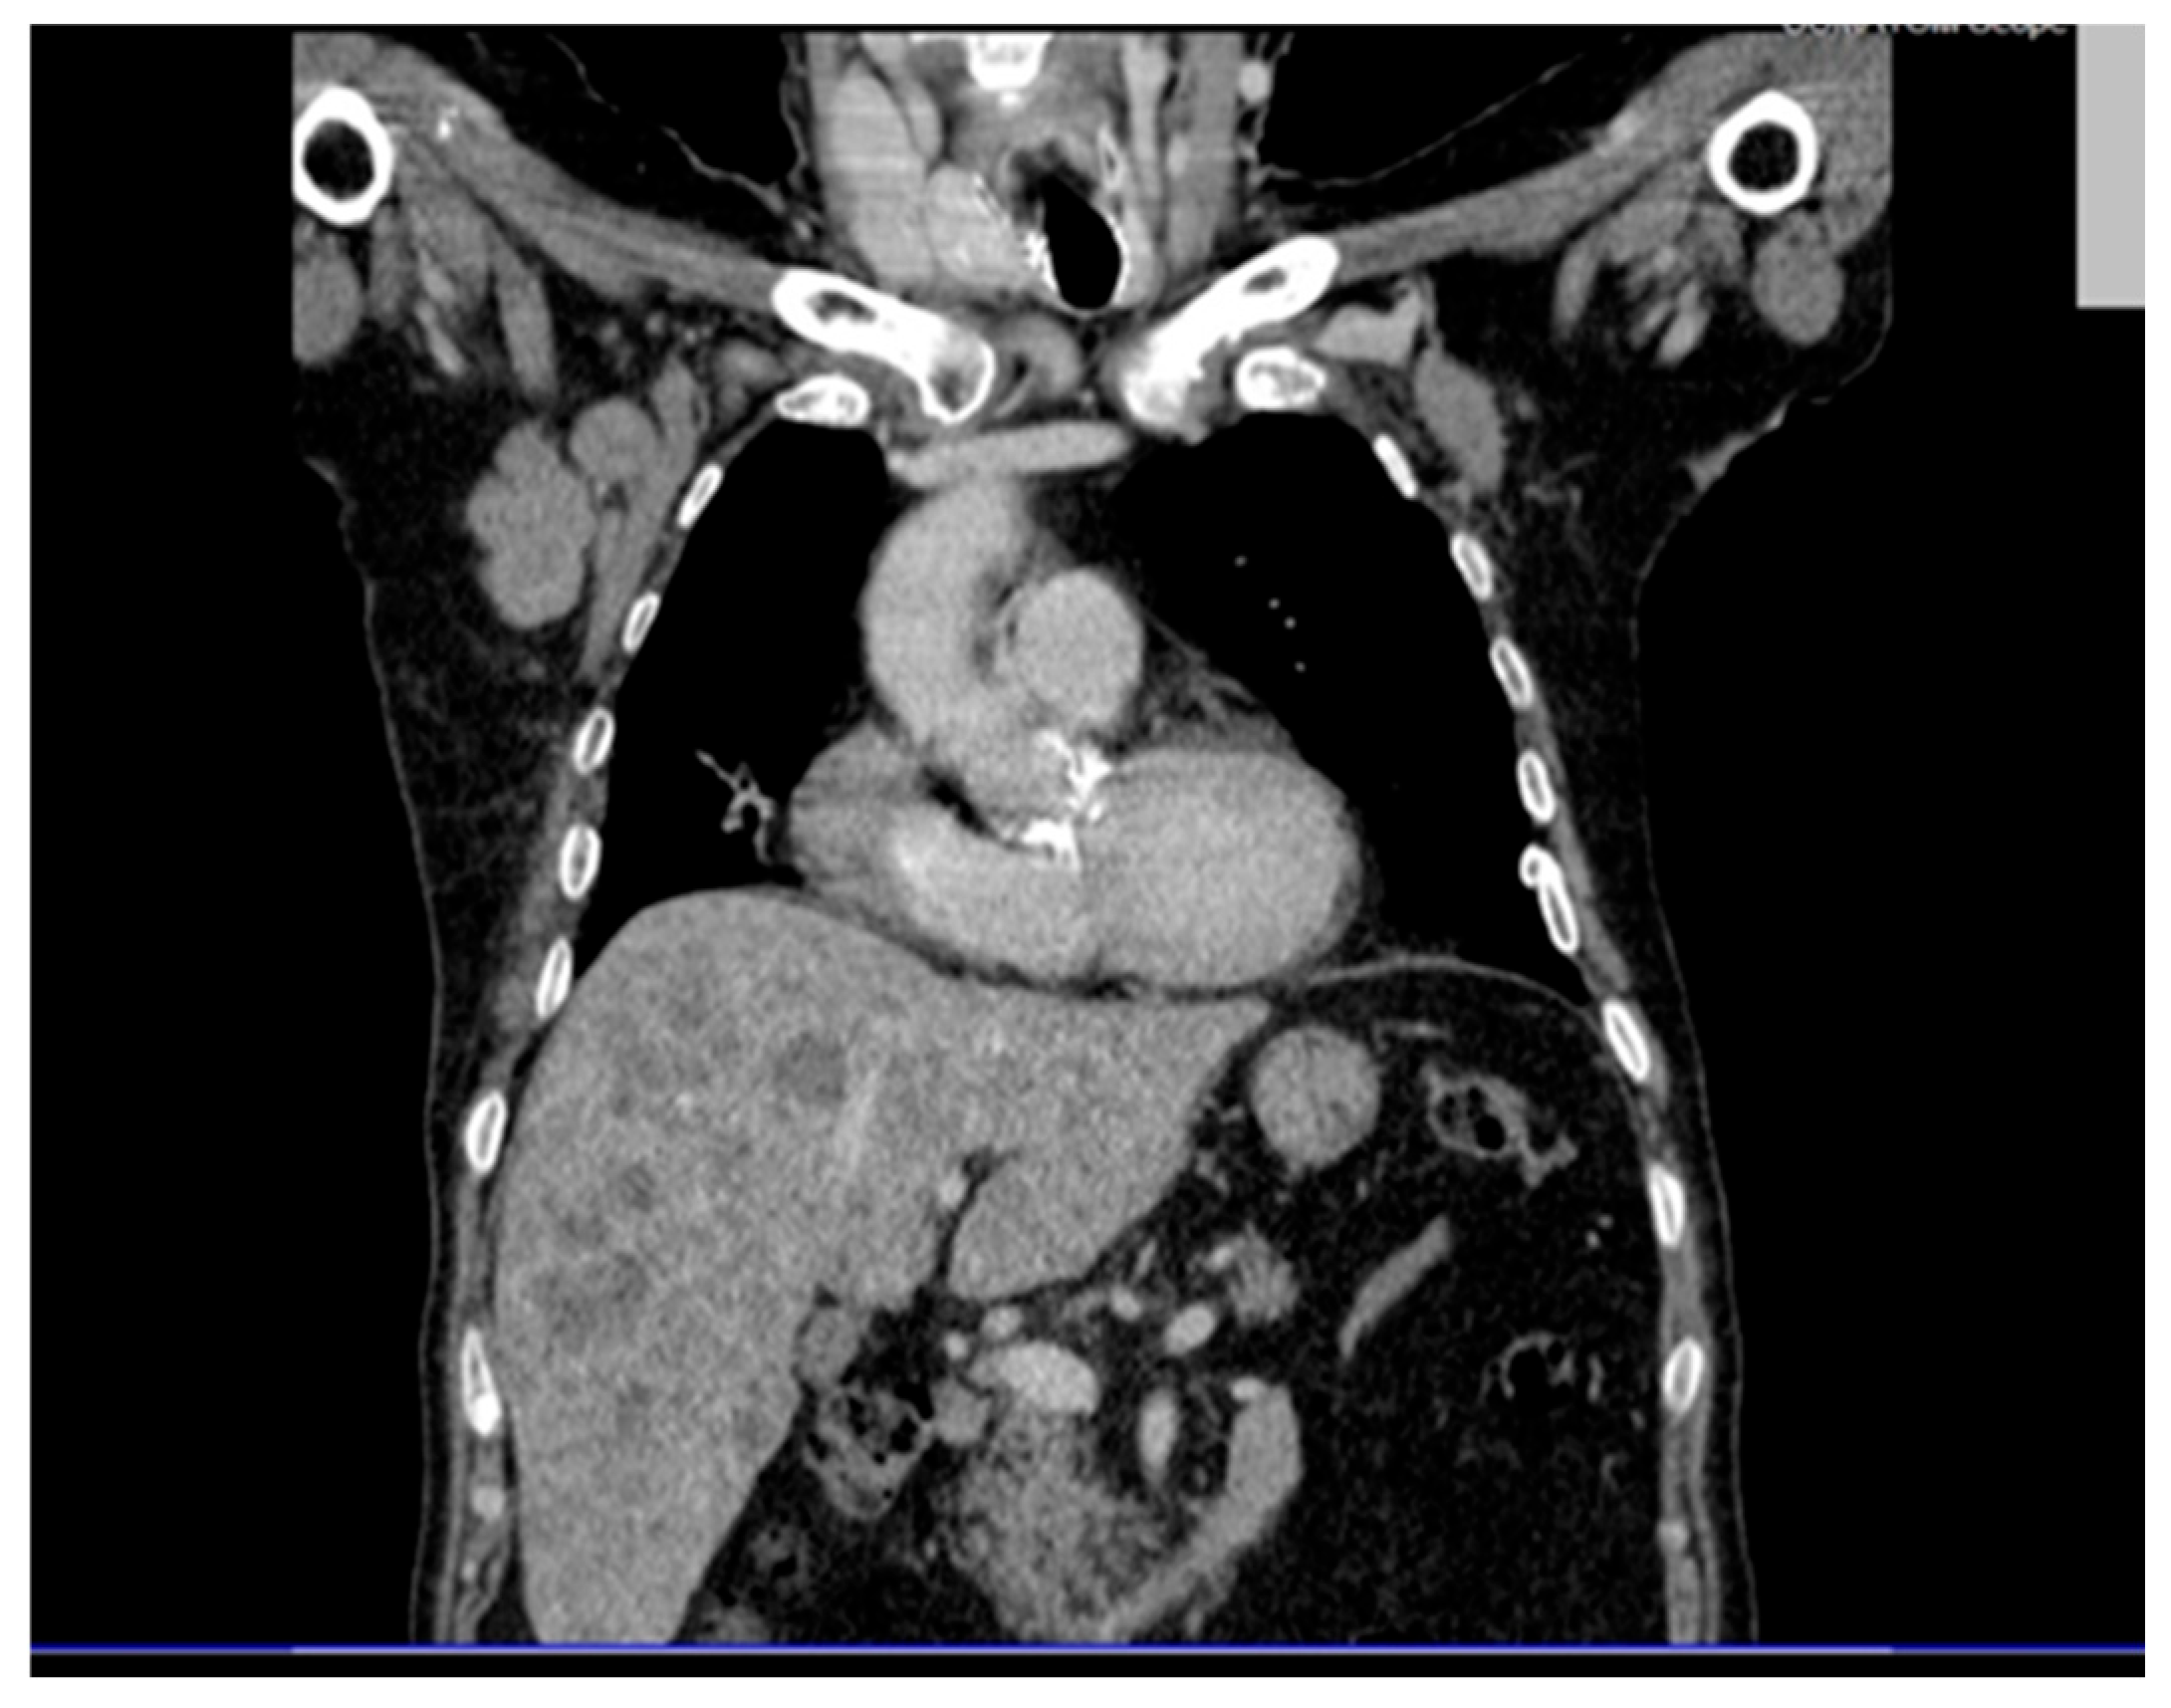

Thoracic CT (contrast and non-contrast) (Figure 2) revealed pleural thickening up to 9 mm posterior to the right lower lobe and along the right oblique fissure extending towards the left upper lobe, along with a band of atelectasis in the middle lobe. Significantly enlarged right axillary lymph nodes were observed, measuring up to 32 × 41 mm.

Figure 2. Contrast-enhanced thoracic CT scan showing pleural thickening up to 9 mm in the posterior segment of the right lower lobe and along the right oblique fissure, as well as a linear atelectasis in the middle lobe. Enlarged right axillary lymph nodes are also noted, measuring up to 32 × 41 mm.